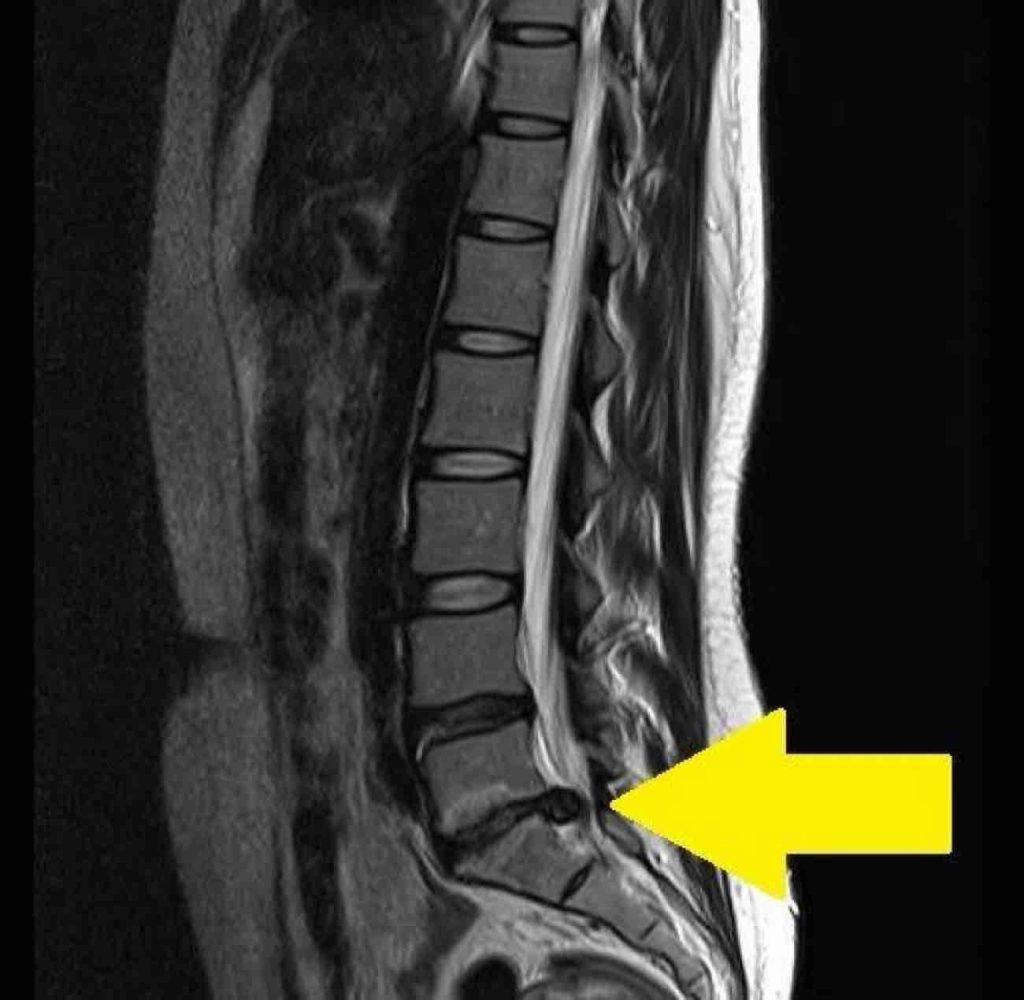

先日、動けないほど腰が痛くなり、病院に行き検査をしたところ、しっかりヘルニアになってしまいました。。

※画像はサンプルです。